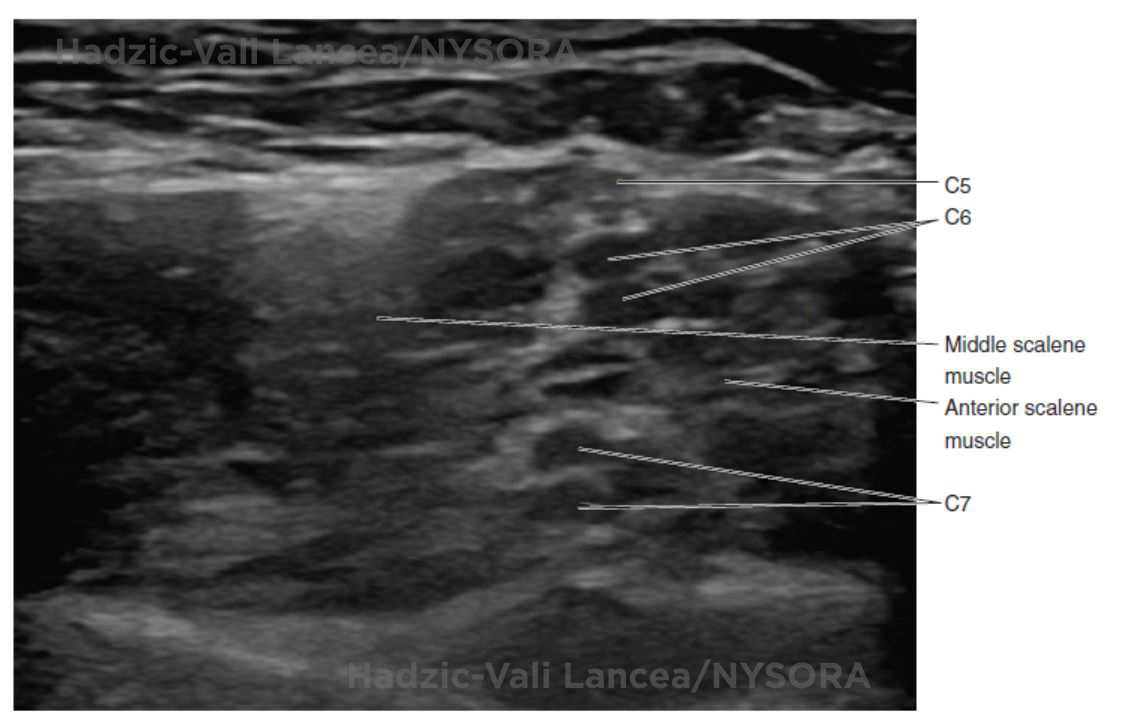

UltrasoundGuided Interscalene Brachial Plexus Block NYSORA The New

from www.nysora.com